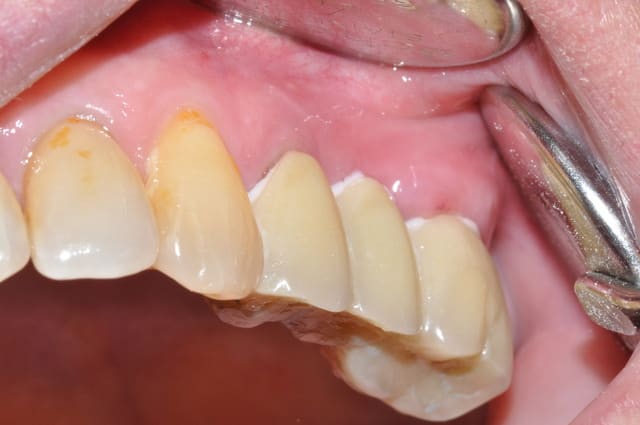

je rassure les puristes la photo a été faite pendant la prise du ciment temporaire

a l'interrogatoire elle sent son bridge coté droit qu'elle ne sentait pas avant

on verra l'évolution mais je pense que les douleurs vont s'estomper

que proposez vous pour reconstruire?